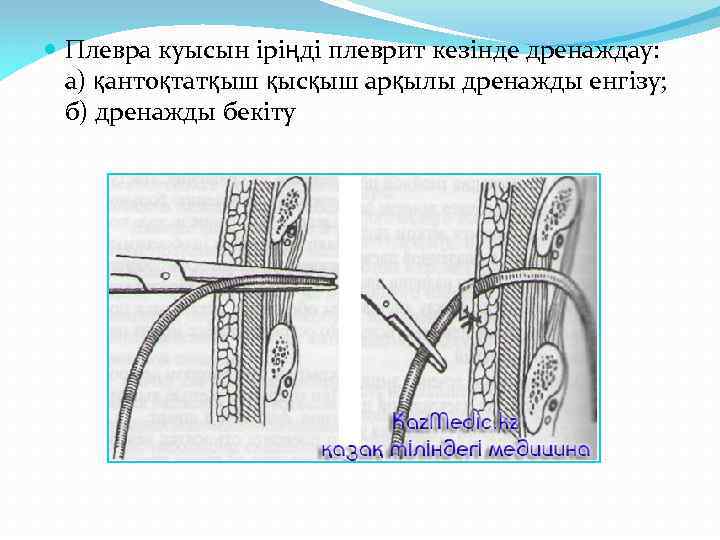

Плевра куысын іріңді плеврит кезінде дренаждау: а) қантоқтатқыш қысқыш арқылы дренажды енгізу; б) дренажды бекіту